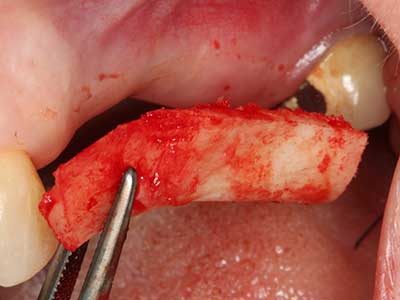

Piezosurgery has additional advantages when harvesting bone blocks. In addition to the high precision with osteotomy described above, the use of the thin saw tips specifically minimizes loss of material. Greater loss of material during harvesting can be expected with the thicker instrument tips, particularly when using Lindemann drills (Lakshmiganthan, Gokulanathan et al. 2012). The basal separation, which is necessary particularly for retromolar block transplants, is simplified by specially designed rectangular saws, with the result that piezosurgery is viewed as a precise, simple and safe procedure for harvesting retromolar bone blocks (Happe 2007) (Fig. 1-12).

Fig. 3: Basal separation of the block is easier with specially angled attachments.

Fig. 4: Additional autologous bone chips are harvested with the bone scaler.